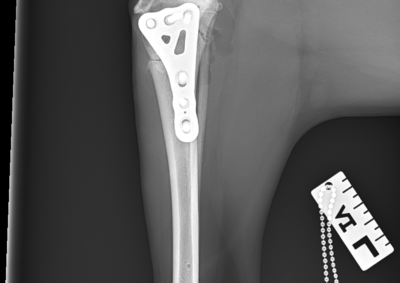

注意 ボタンをクリックした先に、治療中および手術中の画像が説明で使用されている場合がございます。 そのような画像に弱い方は閲覧なさらないようお願いいたします。 整形外科 若齢犬の橈骨固定術 #271 整形外科 前十字靭帯断裂(中型犬)に対するCBLO #255 整形外科 超小型犬に対する上腕骨遠位Y字骨折 整形外科 大型犬の前十字靭帯疾患(慢性経過)に対するCBLO #254 整形外科 橈骨固定術 #270 整形外科 膝蓋骨内方脱臼に対する人工滑車置換術 PGR #23 整形外科 犬の前十字靭帯(疾患)部分断裂に対するCBLO #253 整形外科 犬の前十字靭帯断裂に対するCBLO #252 整形外科 膝蓋骨内方脱臼+前十字靭帯断裂に対するPGR#22・LSS 整形外科 大腿骨骨折 整形外科 橈骨固定術 #269 整形外科 上腕骨外顆骨折の癒合不全 123456> 症例カテゴリー 放射線治療整形外科軟部組織外科脳神経外科内科腫瘍外科救急・集中治療リハビリテーション科腫瘍内科内視鏡科脳神経科呼吸器外科中医・漢方猫の腎移植循環器科